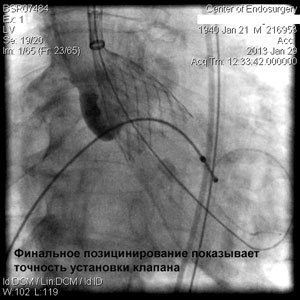

Через прокол (или маленький разрез) в артерии, в сжатом состоянии проводят искусственный клапан, который расширяется при его установке на месте поврежденного аортального клапана. После раскрытия клапан начинает функционировать и восстанавливает полноценную и нормальную работу аорты.

Впервые в России частная многопрофильная клиника «Центр эндохирургии и литотрипсии», опираясь только на собственные ресурсы и не расходуя бюджетные средства на здравоохранение, выполнила эту уникальную и высокотехнологическую операцию у двух пациентов в возрасте 74 и 82 года.